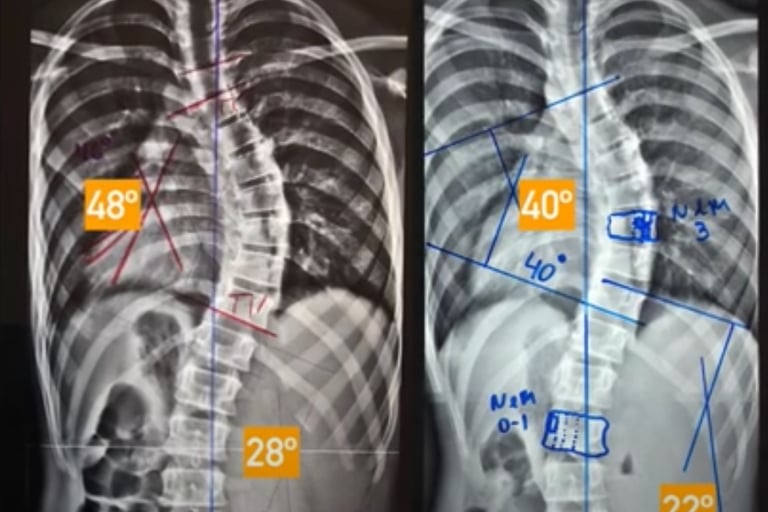

Após receberem o diagnóstico de escoliose, essa família buscou a opinião de diversos ortopedistas renomados, todos unânimes em recomendar a cirurgia de artrodese como única solução.

Aqui, após uma avaliação especializada e detalhada, foi possível substituir o antigo colete Milwaukee — que já não apresentava evolução — por um moderno colete 3D, desenvolvido com base na tecnologia de escaneamento corporal e evidências científicas.

Paciente Adolescente

O resultado?

➡️ Redução de 8° na curvatura torácica

➡️ Redução de 6° na curvatura lombar

Sem cirurgia. Sem internações. Apenas com a combinação de tecnologia avançada, atendimento especializado e a determinação da família.